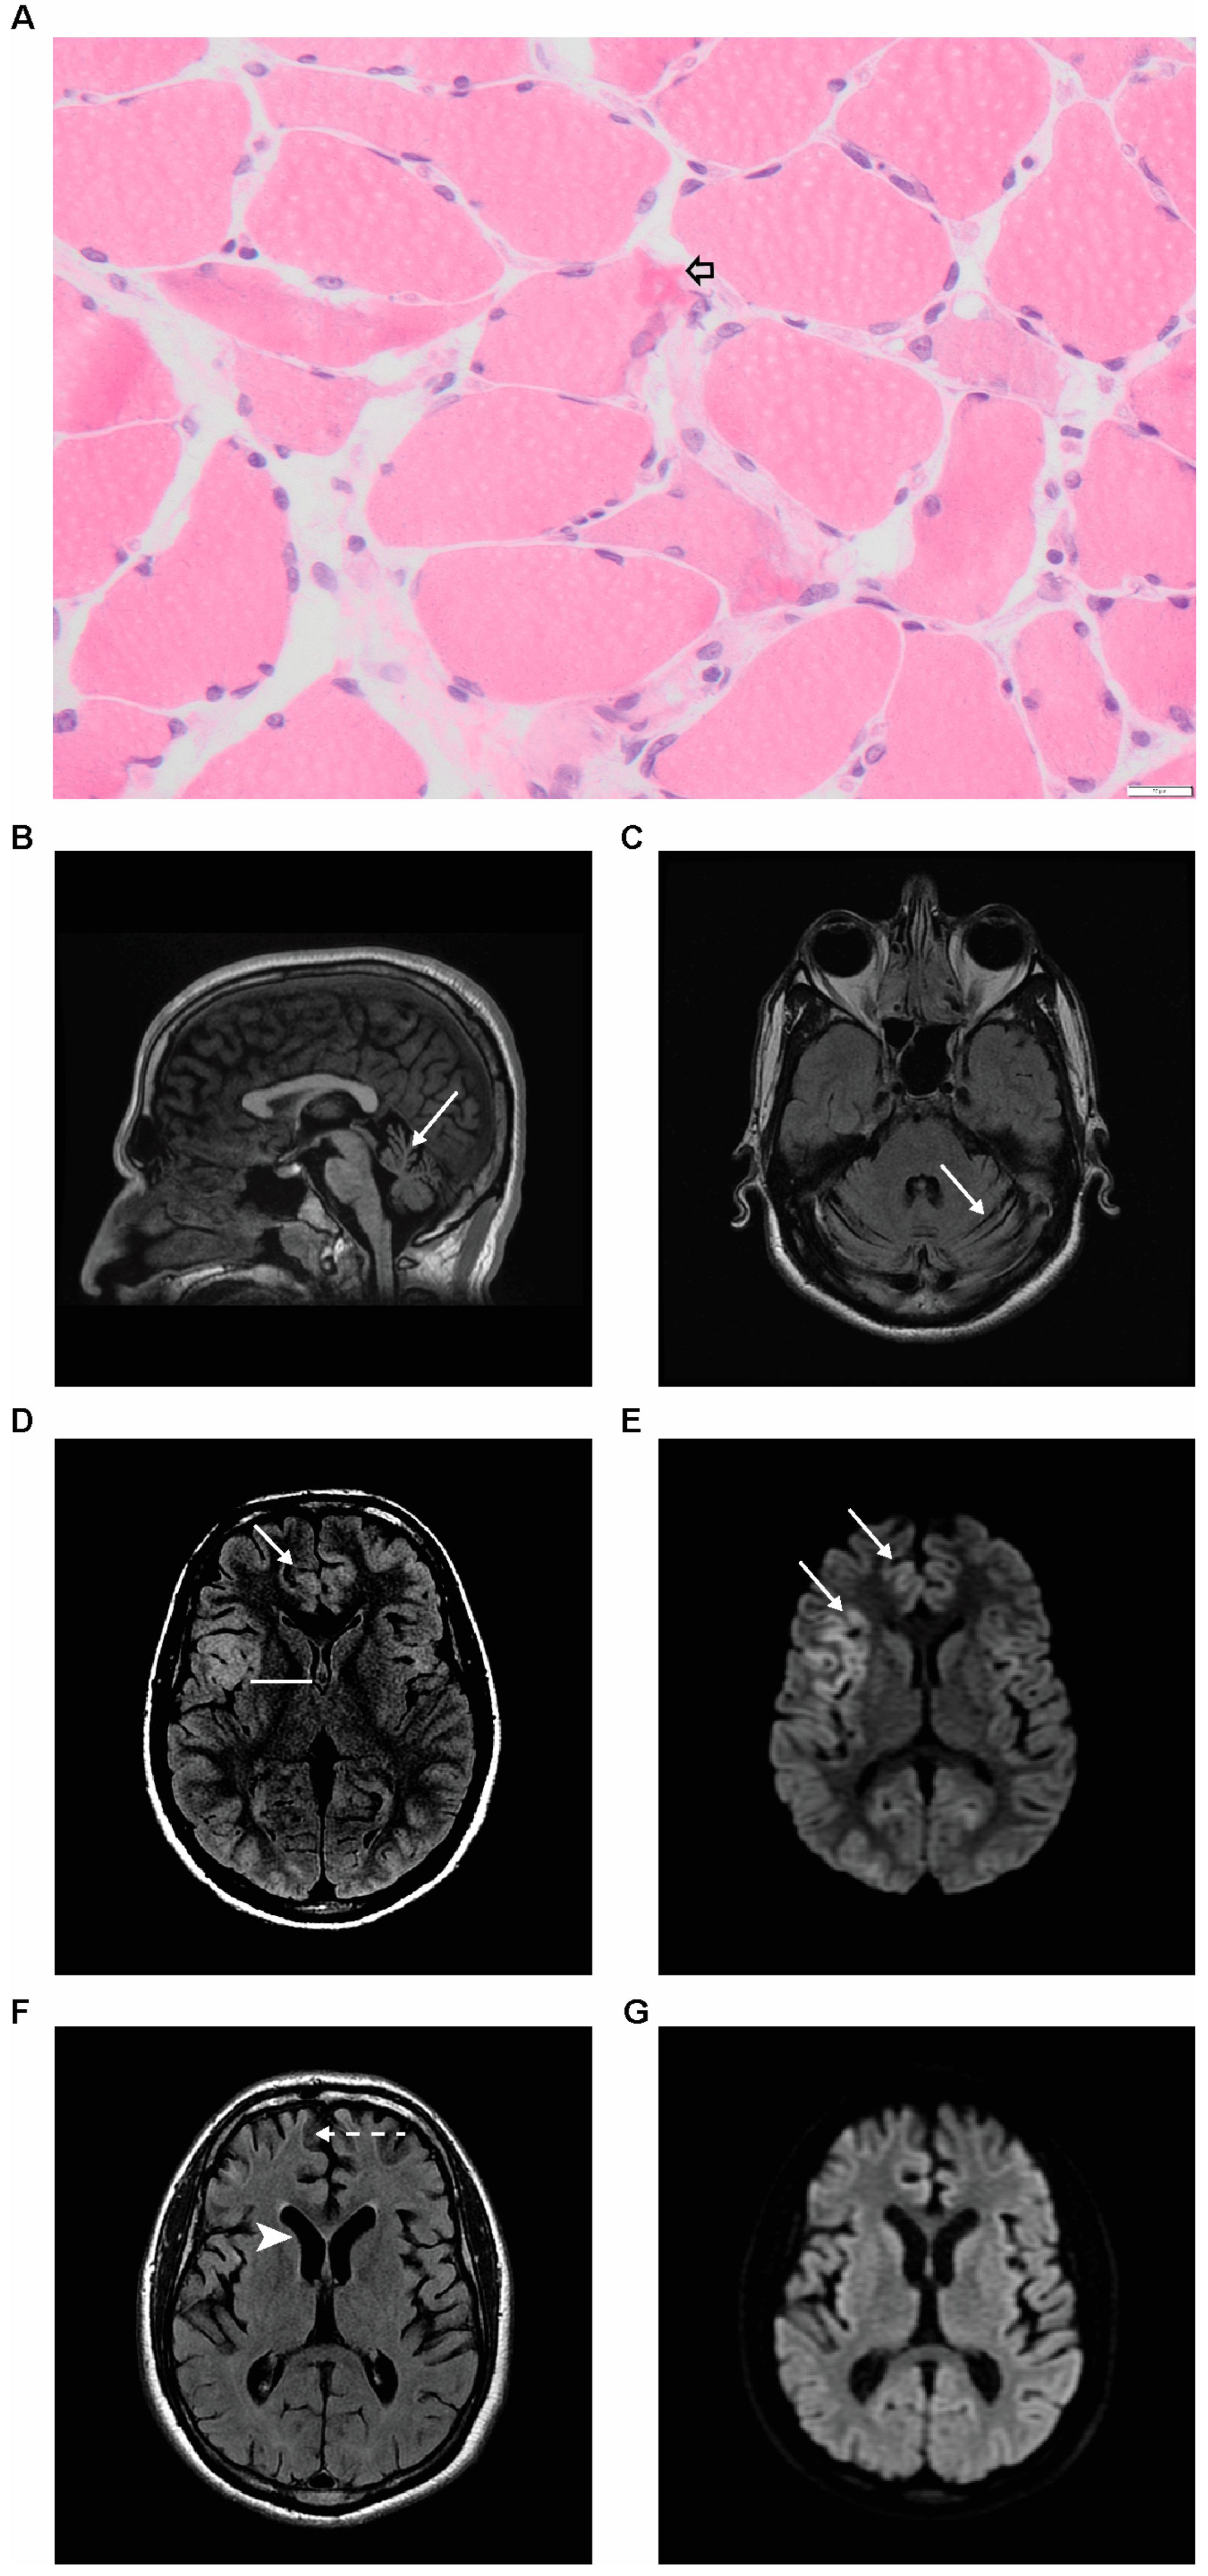

2. Case Presentation

2.1. Proband